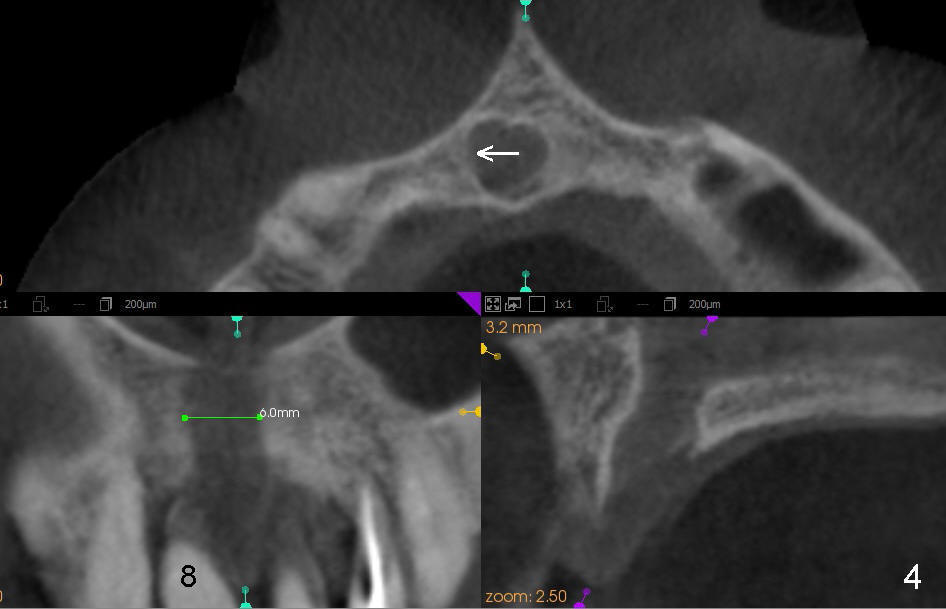

CT研究表明当切牙管小时(图一:I(Incisive Canal),二毫米左右),它比较对称,位于中切牙牙根之间(8,9)。当它大时(五六毫米),它可能对称(图二)或者不对称(图三,四),接近一个(图三,四)或者两个(图二)牙根,造成植牙困难。